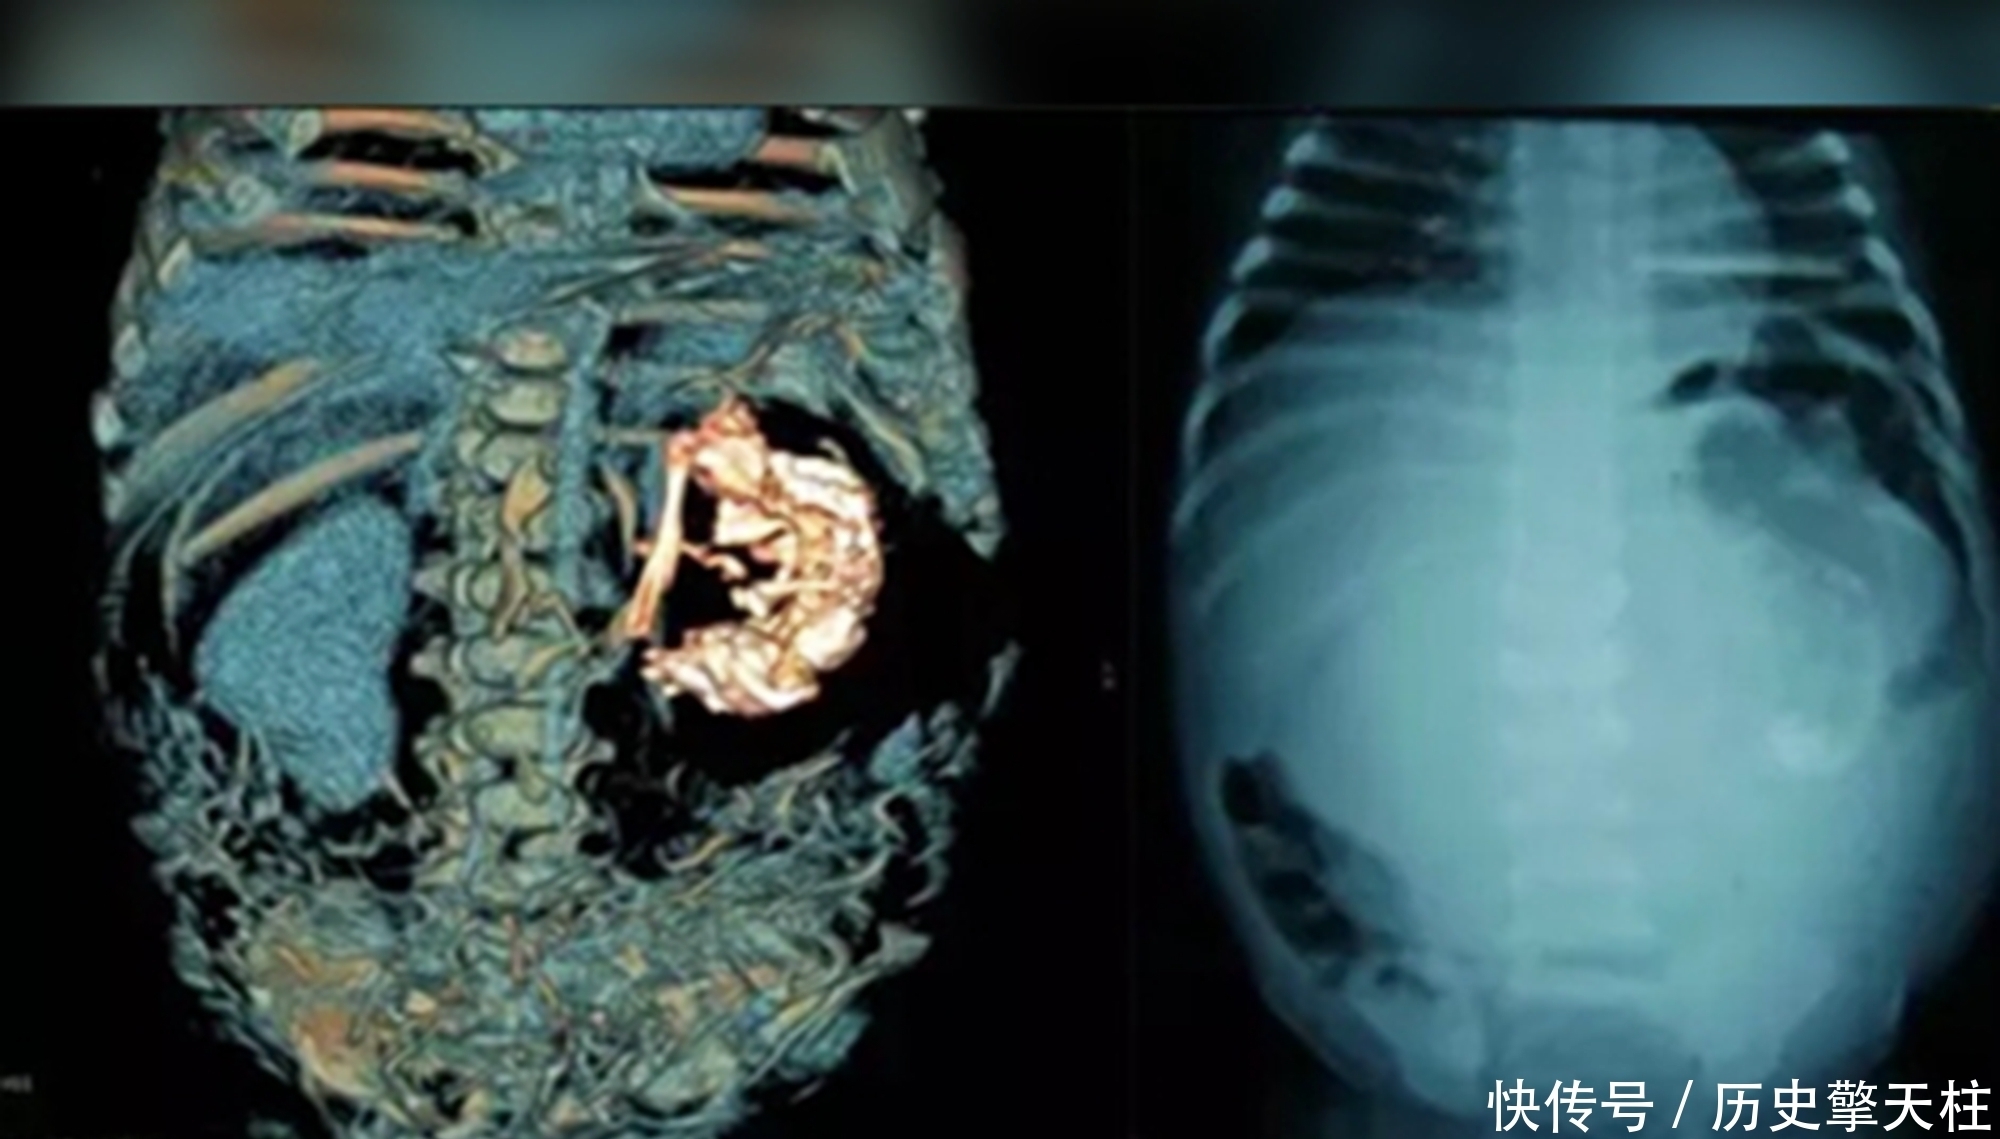

父母带梅迪纳去了镇上的医院后,主治医生起初以为是肿瘤,经过X光检查和验血,诊断结果出来后,却得到了一个令人震惊的结果——梅迪纳怀孕了!当时不过5岁六个月的梅迪纳,居然有了7个月的身孕。

因生育年龄实在太小,众人纷纷猜测是“寄生胎”,却被医生否认

不到六岁就生孩子?放在现在都算是奇闻,这个年纪的孩子本该在上幼儿园,大众认知中的人体生理构造,也让人很难相信,这名男婴是梅迪纳孕育的,纷纷提出猜测,而呼声最高的便是“寄生胎”。

这一说法并非空穴来风,新闻报道中那些小女孩甚至是小男孩,生孩子的稀奇案例,大多都是“寄生胎”在作祟,而这其实并不是真正意义上的“生孩子”,在医学上归属于连体婴的一种。

文章图片

说白了就是,孕妈怀了双胞胎后,因某种特殊原因一个胚胎将另一个胚胎“纳入其中”,这样的寄生胎,有的并不影响存活下来的那个宝宝的生长发育,甚至能在其体内寄生几十年都不被发现,这种病变,在新生儿中出现的概率约为50万分之一。

“寄生胎”其实并不是正常胎儿,它们大多存在一定程度上的畸形,根本没有生命,更不可能被“生”下来,而梅迪纳的孩子确实健康的男婴,一直活到40多岁才因病去世,这和“寄生胎”理论是相悖的。